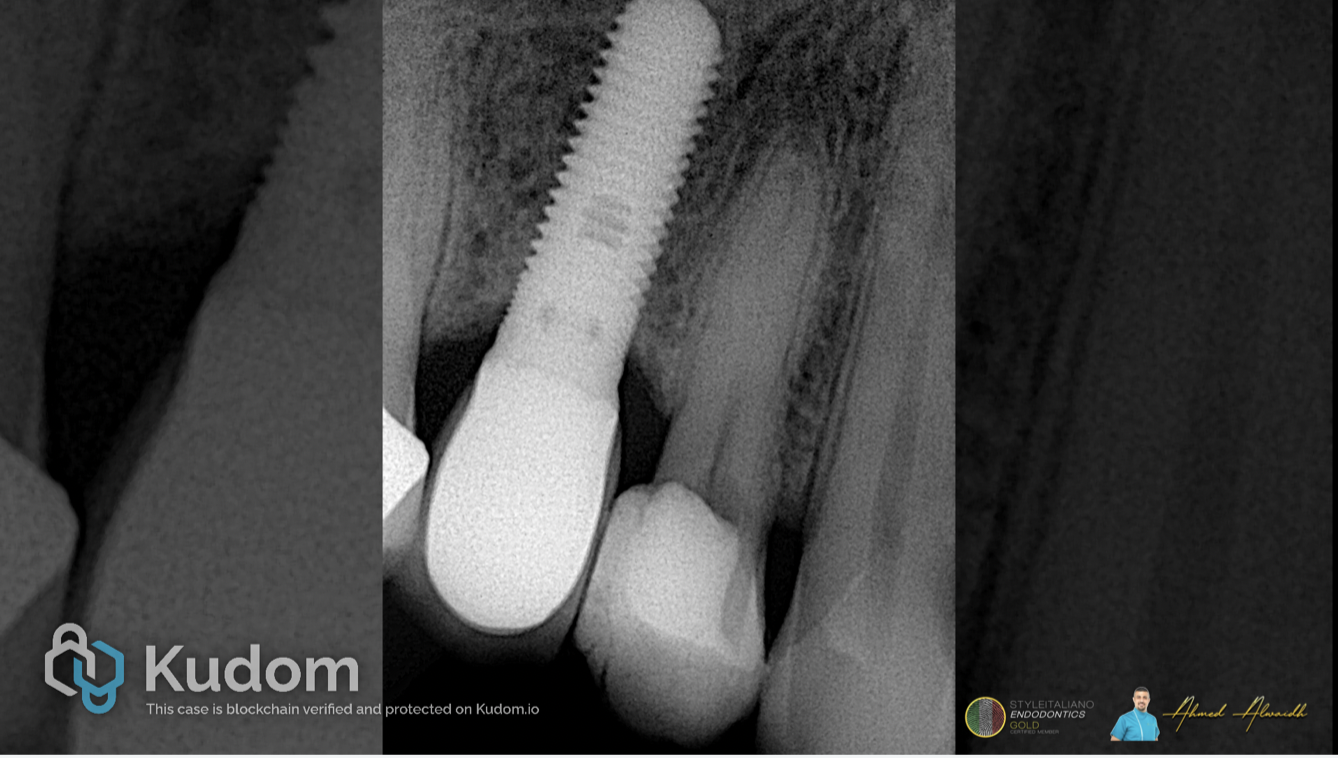

Fig. 1

Pre-operative IOPA showed narrow and calcified canals